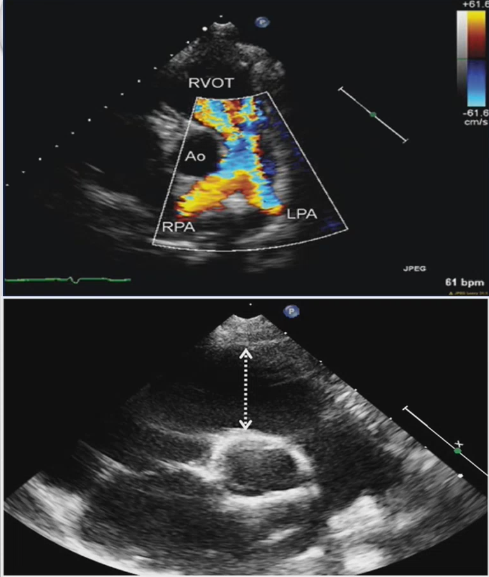

A

Pulmonary regurgitation, (no pulmonary valve) the regurgitation star before the pulmonary valve

this is Tetrology of fallot after repair